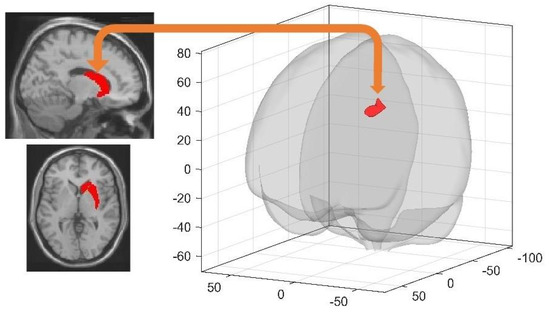

| Left Retrosplenial Cortex | Left Superior Frontal Gyrus | −16 12 48 | 738 | 5.91 | 0.000000 |

| Right Middle Frontal Gyrus | 28 6 56 | 390 | 5.78 | 0.000047 | |

| Right Entorhinal Cortex | Right Superior Frontal Gyrus | 18 24 56 | 228 | 5.25 | 0.001829 |